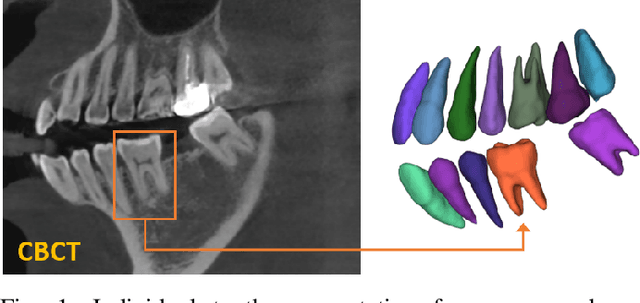

Abstract:Individual tooth segmentation and identification from cone-beam computed tomography images are preoperative prerequisites for orthodontic treatments. Instance segmentation methods using convolutional neural networks have demonstrated ground-breaking results on individual tooth segmentation tasks, and are used in various medical imaging applications. While point-based detection networks achieve superior results on dental images, it is still a challenging task to distinguish adjacent teeth because of their similar topologies and proximate nature. In this study, we propose a point-based tooth localization network that effectively disentangles each individual tooth based on a Gaussian disentanglement objective function. The proposed network first performs heatmap regression accompanied by box regression for all the anatomical teeth. A novel Gaussian disentanglement penalty is employed by minimizing the sum of the pixel-wise multiplication of the heatmaps for all adjacent teeth pairs. Subsequently, individual tooth segmentation is performed by converting a pixel-wise labeling task to a distance map regression task to minimize false positives in adjacent regions of the teeth. Experimental results demonstrate that the proposed algorithm outperforms state-of-the-art approaches by increasing the average precision of detection by 9.1%, which results in a high performance in terms of individual tooth segmentation. The primary significance of the proposed method is two-fold: 1) the introduction of a point-based tooth detection framework that does not require additional classification and 2) the design of a novel loss function that effectively separates Gaussian distributions based on heatmap responses in the point-based detection framework.

Abstract:Individual tooth segmentation from cone beam computed tomography (CBCT) images is an essential prerequisite for an anatomical understanding of orthodontic structures in several applications, such as tooth reformation planning and implant guide simulations. However, the presence of severe metal artifacts in CBCT images hinders the accurate segmentation of each individual tooth. In this study, we propose a neural network for pixel-wise labeling to exploit an instance segmentation framework that is robust to metal artifacts. Our method comprises of three steps: 1) image cropping and realignment by pose regressions, 2) metal-robust individual tooth detection, and 3) segmentation. We first extract the alignment information of the patient by pose regression neural networks to attain a volume-of-interest (VOI) region and realign the input image, which reduces the inter-overlapping area between tooth bounding boxes. Then, individual tooth regions are localized within a VOI realigned image using a convolutional detector. We improved the accuracy of the detector by employing non-maximum suppression and multiclass classification metrics in the region proposal network. Finally, we apply a convolutional neural network (CNN) to perform individual tooth segmentation by converting the pixel-wise labeling task to a distance regression task. Metal-intensive image augmentation is also employed for a robust segmentation of metal artifacts. The result shows that our proposed method outperforms other state-of-the-art methods, especially for teeth with metal artifacts. The primary significance of the proposed method is two-fold: 1) an introduction of pose-aware VOI realignment followed by a robust tooth detection and 2) a metal-robust CNN framework for accurate tooth segmentation.